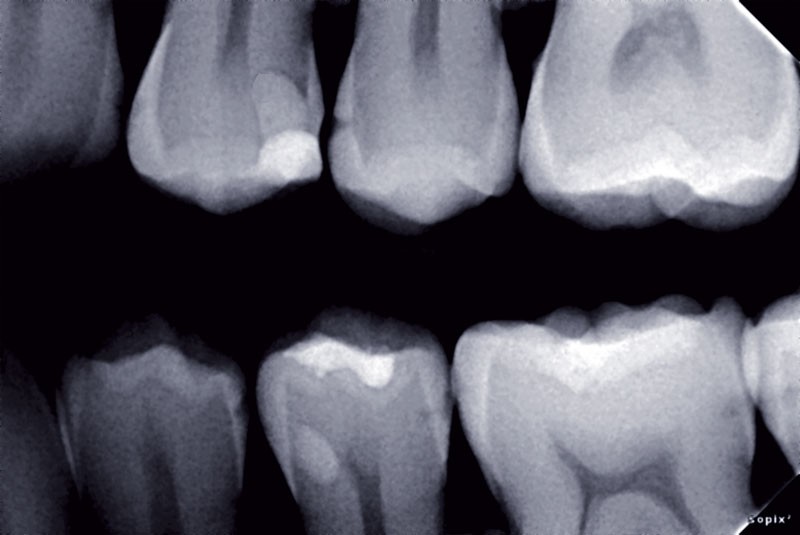

L’approche médicale des lésions carieuses dentaires requiert une détection de ces lésions à un stade le plus précoce possible. Les nouvelles méthodes de détection sont basées sur : la transmission de lumière, la fluorescence (systèmes de fluorescence uniquement, combinaison de caméra et système de fluorescence), l’impédance électrique et la conductivité. Le diagnostic établi sera plus ou moins fiable et précis selon l’aide visuelle utilisée et l’expérience de l’opérateur. Ces techniques nous permettent d’établir un diagnostic de lésions précoces et par conséquent de réaliser des traitements préventifs et a minima afin de conserver au maximum les tissus sains ou de contrôler l’évolution de lésions débutantes en cas d’abstention thérapeutique.

L’approche médicale des lésions carieuses dentaires requiert une détection de ces lésions à un stade le plus précoce possible. La gestion du risque carieux et le développement de technologies pour détecter et quantifier ces caries précoces ainsi que l’activité carieuse seront des outils pour identifier des patients nécessitant une intervention préventive intensive (1). Ces méthodes de détection et quantification des lésions carieuses nécessitent certaines conditions : des contrôles réguliers, être capable de détecter des lésions précoces, de différencier des lésions superficielles de celles plus profondes (haute sensibilité), présenter si possible des données quantitatives de sorte que l’activité puisse être surveillée ; être précis afin que les mesures puissent être répétées par plusieurs opérateurs, être rentables et faciles à utiliser. De nouvelles classifications sont apparues (ICDAS, Univiss) et la principale requête est d’être sûr que le dispositif de diagnostic et la classification utilisée soient parfaitement adaptables à une pratique quotidienne (2).

Les nouvelles méthodes de détection sont basées sur la transmission de lumière et la fluorescence.

Transmission de lumière

a) transillumination par fibre optique (Foti®, Difoti®, Electro-Optical Sciences) et plus récemment une technique numérisée Difoti® qui utilise la transmission de la lumière à travers la dent. Ainsi les images peuvent être stockées et réexaminées plus tard (3, 4, 5).

b) Camera Kavo®: DIAGNOcam® (Kavo Dental) : un nouveau système développé récemment par Kavo est également basé sur le niveau élevé…